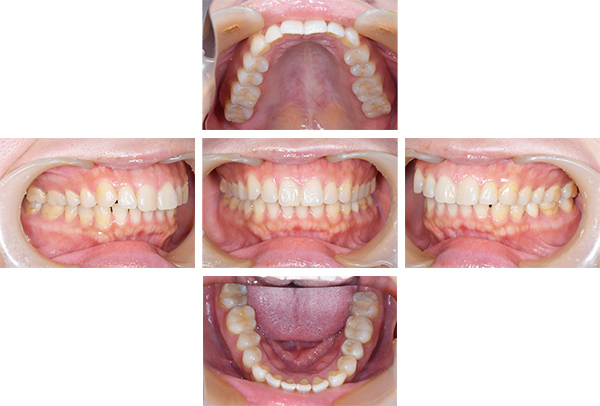

症例写真(治療前)

担当医師所見

治療前:

八重歯が目立ちます。また銀歯もおおく、見た目が気になります。虫歯も散見できます。

レントゲン写真(治療前)

根の治療を3本すでに治療されています。1本根の奥の詰め物が疎になっていますので、根の部分の再治療も行う必要がありそうです。銀歯の中で虫歯になっているものもあります。

治療中

矯正装置をつけています。だんだん八重歯が動いてきているのがわかります。今回のケースでは、抜歯を行わずに矯正ができました。

症例写真(治療後)

治療後:

矯正治療と虫歯の治療すべて終わったときの写真になります。見た目も最初の頃とは全く違いますし、お口の中もすごく綺麗です。

治療

方針

まずは虫歯の治療を行い、被せ物をする部分は仮歯をいれて矯正を行う。矯正終了後、仮歯の部分を最終的な被せ物に変えていく。また気になっていた銀歯もセラミックに変えて終了となった。

内容

セラミックインレー、オールセラミックプレミアム、矯正